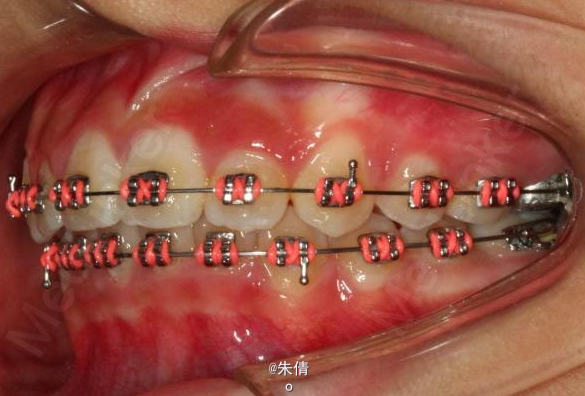

对于面型较好,拥挤度不大的病例,推磨牙向后不失为一种很好的方法,当然现在推磨牙后向的手段和方法很多,但是主要 是适应证的问题。我认为我们在做推磨牙向后,首先是考虑拥挤度,第二个要考虑的是现有的面型,第三点也是很重要的一点,是考虑牙弓后段拥挤度,Tweed-Merryfireld拥挤度的诊断方法将牙弓拥挤度分析分为三段,牙弓前段拥挤度,牙弓中段的拥挤度,以及牙弓后段的拥挤度。不管用什么方法或是手段推磨牙向后,一定不能将牙弓前端矛盾移到牙弓中段或是后段。今天给大家看一直面型,拥挤度不是很大推磨牙向后的病例。希望对大家能有所帮助。